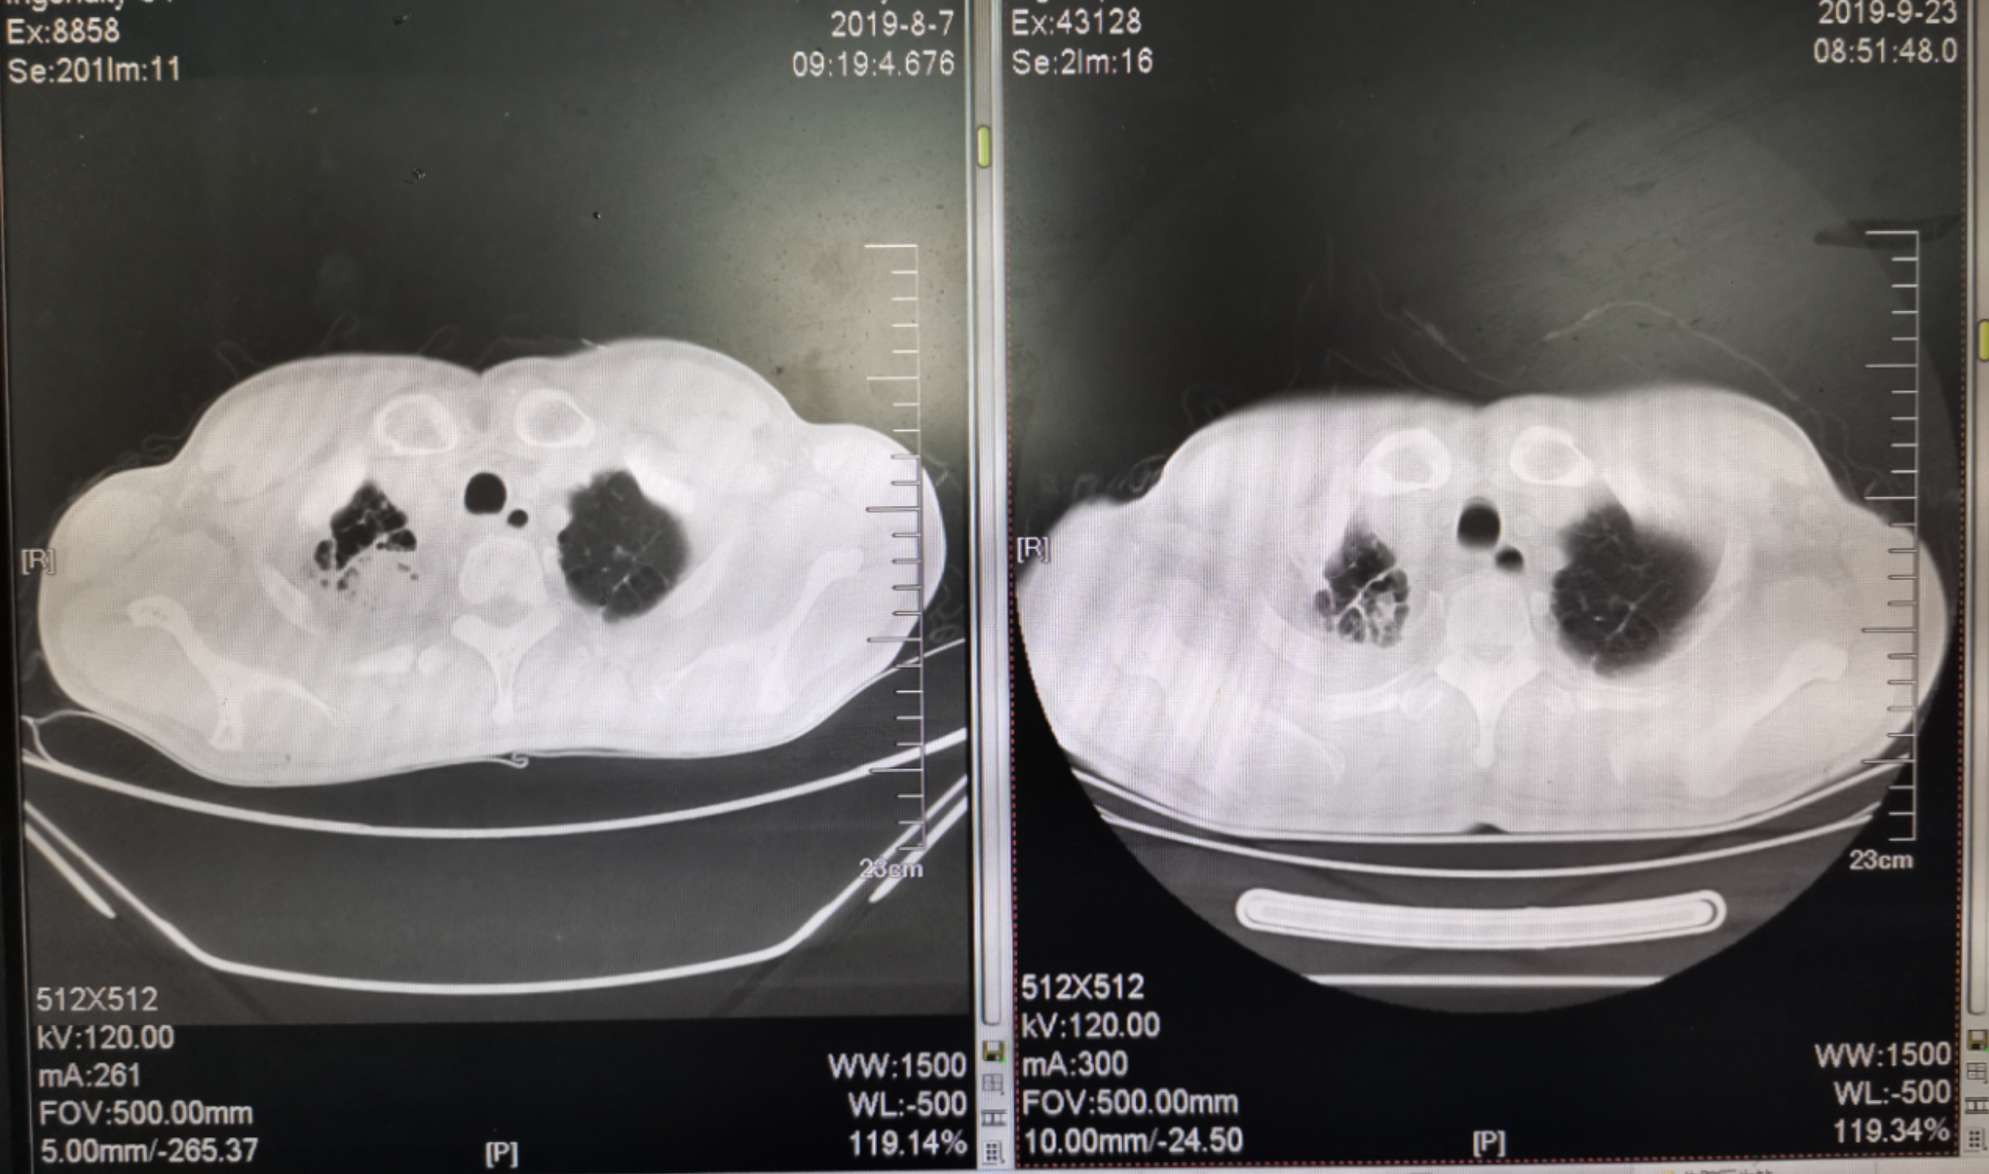

二化联合一k后复查ct对比

左边是上月化疗前的,右边是昨天拍的,今天上了第二次k药,准备明天第三期化疗。

我自己对着拍的,切面对的不是很准确,但大致上看的出来明显小了。